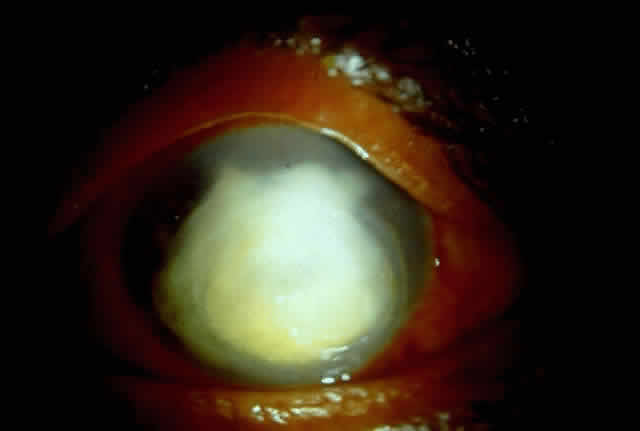

Active corneal infections in advanced stages are encountered more often by corneal surgeons in developing countries compared with their counterparts in developed countries (Fig. 8). The extent of corneal involvement associated with other intraocular damage often compromises the success of corneal transplantation. In a series from our institution, the success rate for graft clarity was poorer24 compared with other series.25 Ophthalmologists involved in corneal surgery should be familiar with this information and be prepared for the necessary intraoperative manipulations (Fig. 9).

Fig. 8. Corneal ulcer with extensive necrosis and perforation in the superior part.